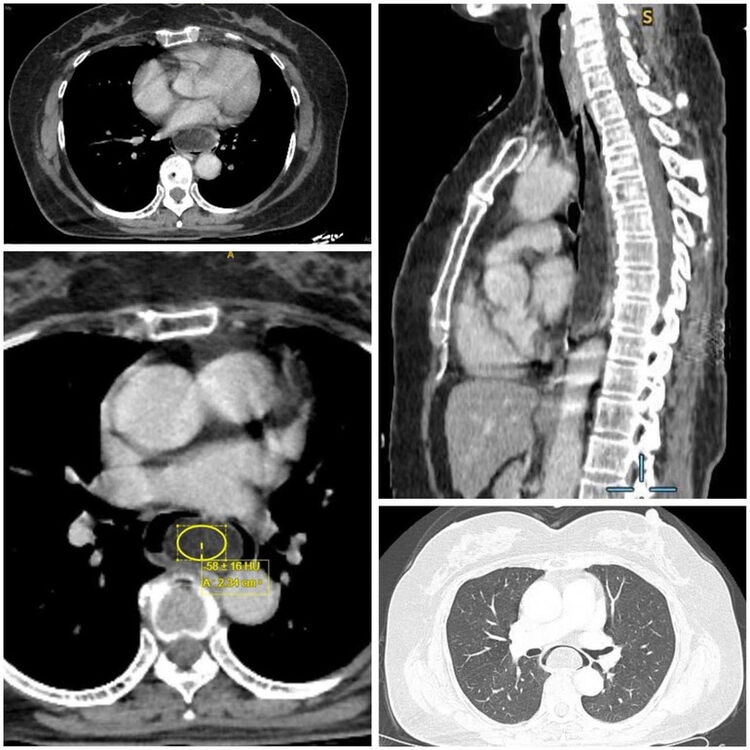

Tiến sĩ, bác sĩ Bùi Ánh Tuyết, Trưởng khoa Nội soi-Thăm dò chức năng, bệnh viện K cho biết, người bệnh vào viện trong tình trạng nuốt nghẹn, đã kéo dài khoảng 6 tháng. Sau quá trình khám lâm sàng, tìm hiểu diễn biến bệnh, thực hiện nội soi và siêu âm nội soi, các bác sĩ kết luận người bệnh có u mỡ thực quản dưới niêm mạc, kích thước 16x3,5x3cm. Đây là khối u có "kích thước khủng", bởi thông thường các khối u dưới niêm mạc đường tiêu hóa có kích thước thường nhỏ hơn 3cm.

Hình ảnh khối u của bệnh nhân có kích thước rất lớn16x3,5x3cm.